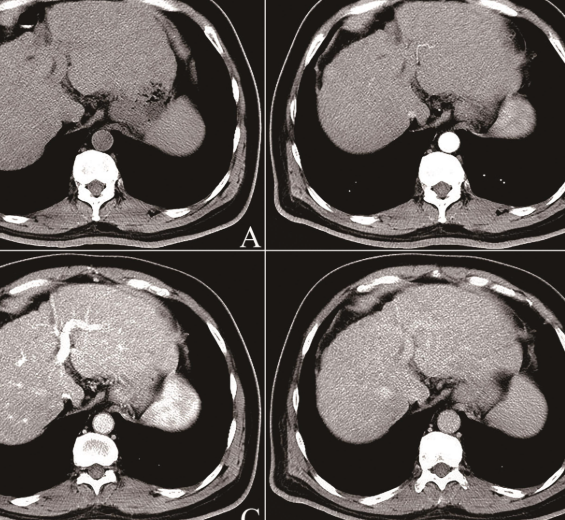

간 결절이란 간 조직 내에서 국소적으로 형성되는 작은 혹 형태 구조물을 말합니다. 주로 초음파, CT, MRI 검사에서 우연히 발견되는 경우가 많으며, 대부분은 양성 변화로 평가됩니다. 하지만 ‘간 결절 치료방법’을 고민하게 되는 이유는, 일부 경우 결절이 커지거나 악성 가능성이 있는 병변으로 의심되기 때문이죠.

생활 중심 관리를 통해 결절 변화가 없거나 안정적이라면, 정기 검진을 지속하면서 변화 여부를 지켜보는 것이 바람직합니다. 하지만 결절의 크기가 커지거나 형태가 불규칙해지는 경우, 전문의 상담을 통해 조직검사나 정밀 영상검사를 고려할 수 있습니다.

전문의와 논의할 수 있는 평가 항목으로는 결절의 크기, 경계 모양, 내부 구조, 혈관성 여부 등이 있으며, 필요한 경우 생검이나 추가 진단을 받을 수 있습니다. 치료 방법은 수술적 접근, 비수술적 관찰, 혈관색전술, 또는 약물적 접근(연구 단계)에 따라 달라질 수 있으니, 반드시 전문의와 충분히 상의해야 합니다.